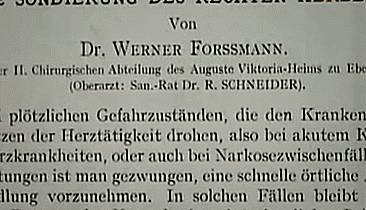

之後,他便把研究成果寫成了論文,報告了心臟導管術及其在診斷、治療上的應用。

同一年的11月,福斯曼在柏林的學會上宣讀了自己的論文。

他本以為自己能憑藉這篇論文,躋身於心臟病學學術圈中。

可誰知道,台下的醫生們卻對他嗤之以鼻。

「靠這些小把戲你可以在一個馬戲團獲得教授資格,但在一個嚴謹的德國醫院,沒門!」

福斯曼的論文

這篇被學術界稱為「小丑表演」的論文在媒體中炸開了鍋,人人都在討論這件駭人聽聞的事。